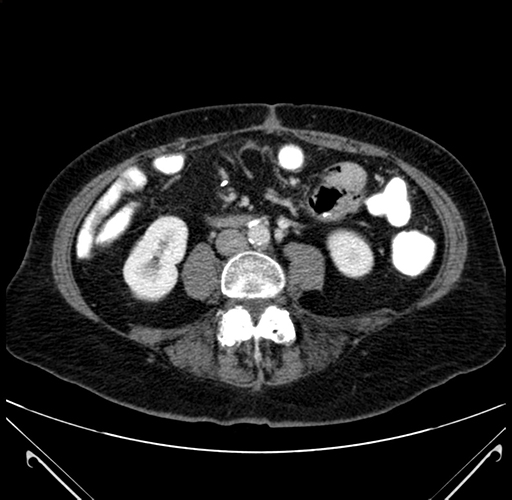

Axial Venous